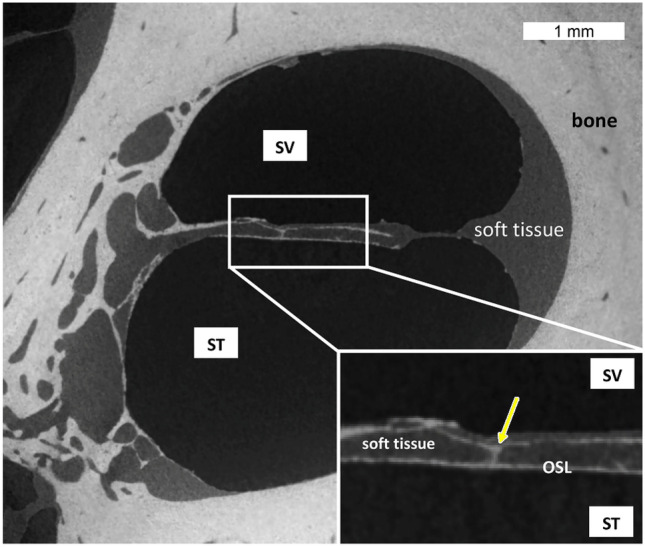

Fig. 3.

MicroCT cross section of the cochlea basal turn demonstrating the OSL and the difference of densities between soft tissue and bone. Yellow arrow points to one pillar that could be seen on the image inset, connecting both OSL plates. SV, scala vestibuli; ST, scala tympani

The OSL is a bony structure suspended inside the cochlea like a “cable-stayed” bridge. Medially, it is connected to the modiolus with rigid bony “cables”. Laterally is connected to the collagen fibers that run along the bridge and basilar membrane, then to the spiral ligament as shown in Raufer et al. [5] with polarized microscopy to visualize collagen fibers. It contains nerve fibers running from the organ of Corti to the SG, seen on the microCT (at 13- and 4.5-µm voxel size resolution) and image as soft density material inside the OSL (Fig. 3).